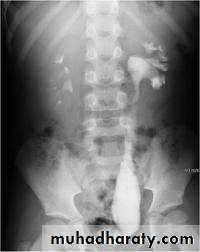

Infantile hydronephrosis ( PUJ OBSTRUCTION ):

IVU shows :

Marked dilatation of pelvis and may be extra-renal.

Calyceal dilatation is late and in advanced cases form foot shape PCS

The ureter is not seen and when it is seen looksnormal .

Delayed film with I.V. diuretic produce gross dilatation .